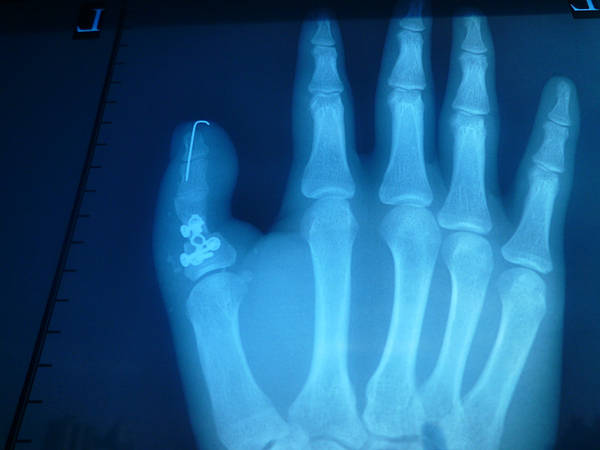

今天拍的术后情况

皮瓣还是没做好有点臃肿!下次注意